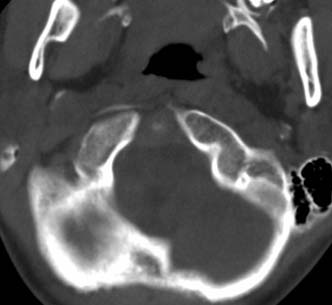

标题: PED0678:男,10岁,寰枢椎平扫。

患者在校与同龄孩子打闹后(据家长说被拳击中颈部)出现颈部不适30分钟后入院检查,来时脖子歪斜。请大家看看枢椎齿状突及寰枢关节有问题吗?(3mm层厚断层扫描)。